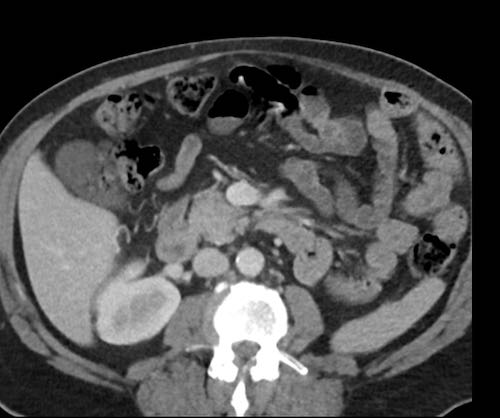

Ca lâm sàng 2

Cuộn qua các lát cắt.

Bạn có thể phát hiện tất cả các tổn thương cấy ghép phúc mạc không?